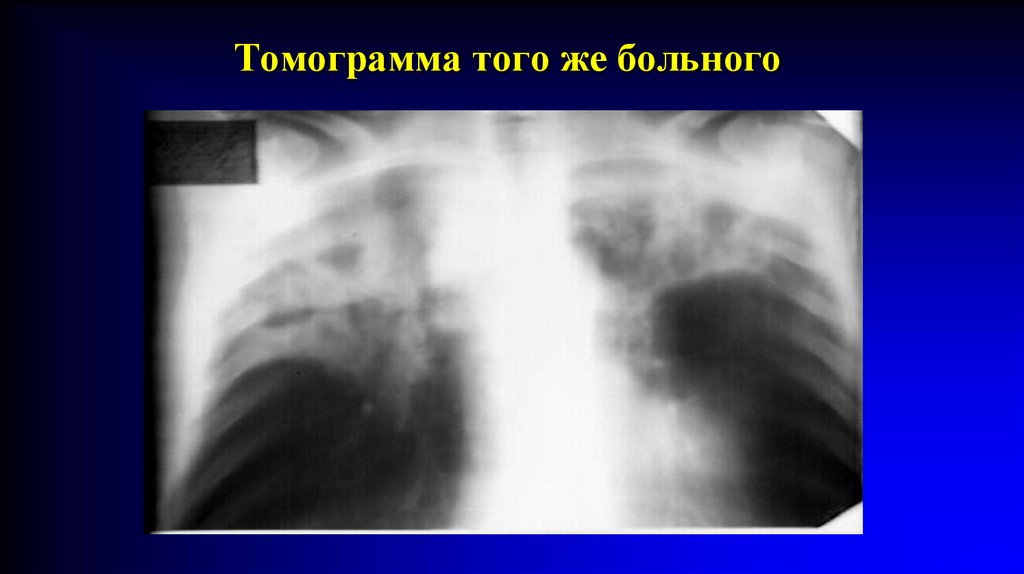

Томограмма того же больного.